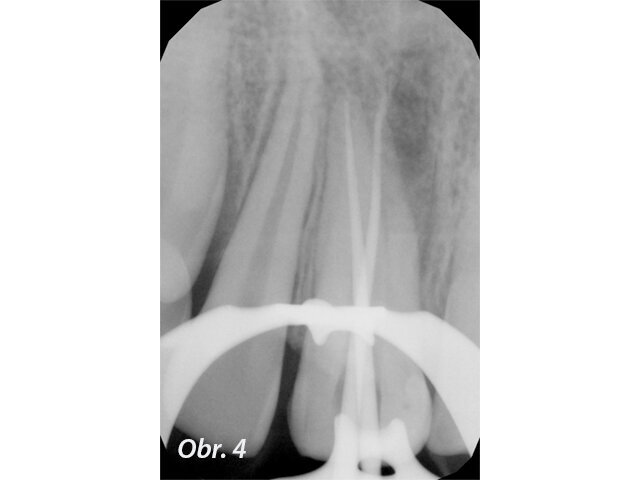

Při klinickém vyšetření nacházíme sanovaný smíšený chrup odpovídající věku pacienta. Zub 11 je poklepově a palpačně nebolestivý, parodontální sondáž je v mezích fyziologické normy. Z vestibulárního pohledu tvarově a velikostně odpovídá kontralaterálnímu zubu (obr. 1), z okluzního pohledu je vestibuloorální rozměr nepatrně větší než u zubu 21 (obr. 2). Šikmá fraktura zubu 11 má meziální okraj cca 1 mm nad okrajem marginální gingivy a distálně zasahuje do incizální třetiny klinické korunky. Dle diagnostického intraorálního rentgenového snímku je ukončen vývoj kořene s přítomným periapikálním nálezem a projasněním na meziálním aspektu kořene. Na ortoradiálním intraorálním rentgenovém snímku, ve srovnání se zubem 21 není jasně zřetelný průběh kořenového kanálku (obr. 3) a na excentrickém rentgenovém snímku je viditelný náznak kontury druhého kořene (obr. 4).

V topické anestezii Lidocain Egis 10 % (EGIS Pharmacaeuticals, Budapešť, Maďarsko) a infiltrační anestezii 1,7 ml Ubistesin (3M ESPE, Maplewood, USA) byl nasazen kofferdam. Po odstranění provizorní výplně byl trepanační otvor více extendován ve vestibuloorálním směru. Byly nalezeny dva vstupy do kořenových kanálků, přičemž vstup do bukálního kořenového kanálku byl protáhlý bukálně a celkově se vstupem do palatinálního kořenového kanálku vytvářely tvar písmene C. Po stanovení pracovních délek pomocí apexlokátoru byly oba kořenové kanálky rotačně opracovány systémem Hyflex CM (Colténe/Whaledent, Akron, USA) až na konečný nástroj ISO 35/04. Mezi jednotlivými nástroji byla preparační drť odplavena výplachem 2,5% chlornanem sodným. Po opracování kořenových kanálků byla provedena aktivace výplachu pomocí ultrazvuku (passive ultrasonic irrigation). Následně byly vyzkoušeny hlavní gutaperčové čepy a zhotoven měřicí intraorální rentgenový snímek v excentrické projekci (obr. 4). Dále byl proveden výplachový protokol 2,5% chlornanem sodným po dobu 20 minut následovaný výplachem 17% roztokem kyseliny ethylendiamintetraoctové po dobu 1 minuty. Na závěr byly kořenové kanálky vypláchnuty 5 ml 2,5% chlornanu sodného. Po vysušení kořenových kanálků papírovými čepy byly kořenové kanálky zaplněny technikou vertikální kondenzace. Ihned po zaplnění byl zhotoven kontrolní intraorální rentgenový snímek v excentrické projekci. Následně byla cavum pulpae očištěna 96% ethanolem a mikroštětečkem. Vnitřní povrch zubu byl opískován a zubní tkáně připraveny technikou total etch a adhezivním systémem Optibond FL.